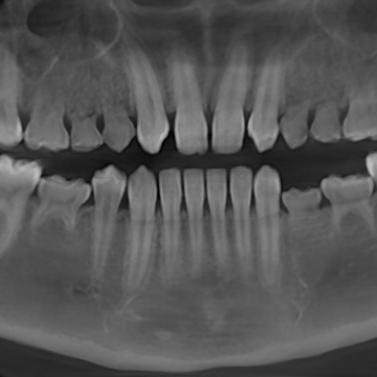

La presentación de casos radiográficos, permite la visualización de patologías que son muy difíciles de ver en la clínica, ya que muchos de ellos son hallazgos radiográficos. Además permite ver y refrescar clasificaciones y conceptos muchas veces estudiados. La presentación de los mismos no incluyen datos personales, mas que edad y sexo, que suelen ser importantes para ver la correlación entre la patología, su aparición o forma de presentación.

Esto también refleja las patologías que aquejan a los pacientes de nuestra región, y trata de ser un faro tanto para profesionales como alumnos que estudian dichas lesiones.